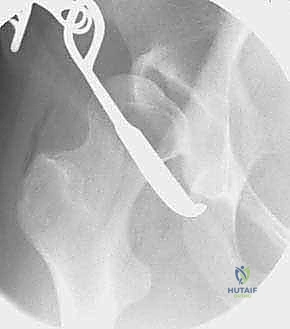

تُعد هذه الجراحة سيمفونية من الدقة الجراحية. تستغرق العملية عادة من 2 إلى 4 ساعات، وتتم تحت التخدير العام أو النصفي المتقدم مع التحكم في الألم (Epidural). إليك تفصيل للخطوات الميكانيكية الدقيقة التي ينفذها الأستاذ الدكتور محمد هطيف باحترافية عالية:

1. النهج الجراحي (The Surgical Approach)

يستخدم الدكتور هطيف شقاً جراحياً تجميلياً يُعرف بـ (Bikini Incision) أو نهج (Smith-Petersen) المعدل. يسمح هذا النهج بالوصول إلى جميع أجزاء الحوض الأمامية والداخلية دون قطع العضلات الرئيسية، بل يتم فصل العضلات وإبعادها بلطف (Muscle-sparing approach)، مما يسرع التعافي بشكل كبير.

2. سلسلة قطع العظام (The 5 Osteotomies)

يكمن سر نجاح جراحة PAO في إجراء خمسة قطوع عظمية منفصلة حول الحُق، لتحريره بالكامل عن باقي الحوض، مع ترك العمود الخلفي سليماً كدعامة أساسية.